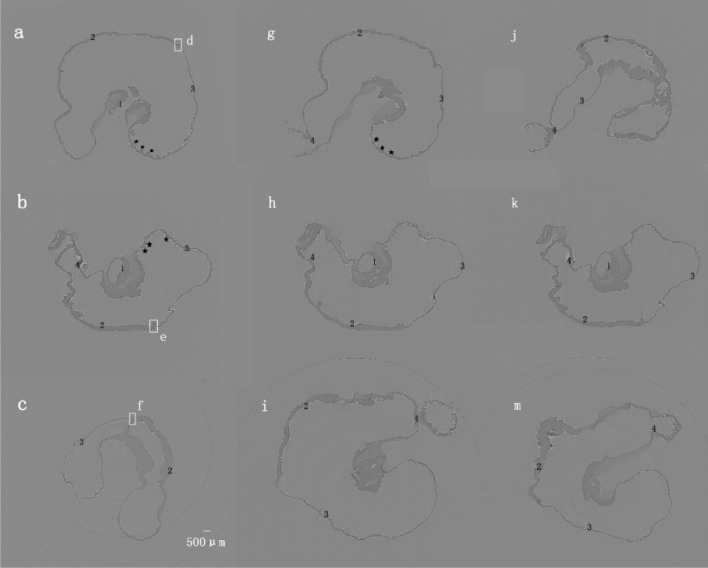

Fig. 3.

The XILPCI transverse CT images of the rats’ gastric specimens in Fig. 1. a The transverse images along the black line a, g and j are shown in Fig. 1. There are transverse CT images of a 4-week-old rat stomach. It can clearly show that there are grey changes in different gastric structures. The thickness of the gastric fundus and corpus are the same as the XILPCI image shows equal width of gastric wall, and it is obvious that there are multiple bulges in the fundus of the 4-week-old rat stomach. b The transverse images along the black line b, h and k as shown in Fig. 1. The XILPCI images show the wider gastric corpus than the fundus but thicker walls of gastric corpus than that of the fundus. This obviously shows that there are grey changes in the different gastric structures and the duodenum. The bulges have decreased in the fundus of the 6-week-old rat stomach. c The transverse images along the black line c, i and m as shown in Fig. 1. It can obviously be seen that there are many gastric corpus wrinkles in the 12-week-old gastric specimen. ★★★ represents the wrinkles of the gastric fundus. 1 Cardia, 2 Gastric Corpus, 3 Gastric Fundus, 4 Pylorus